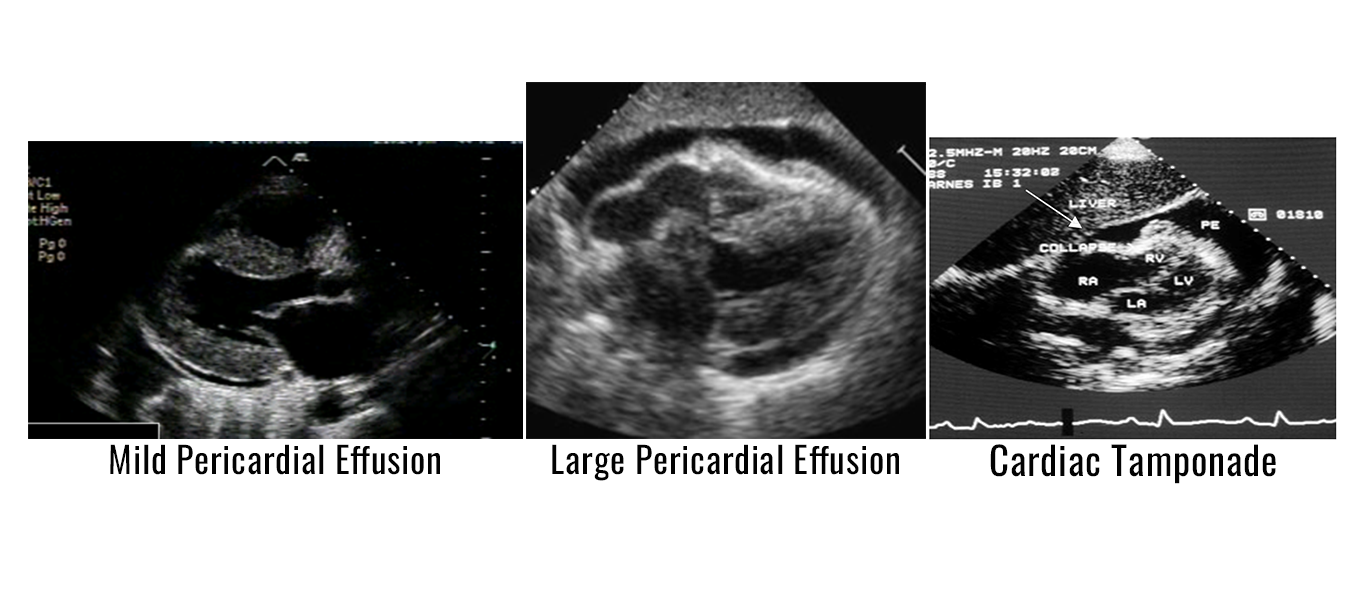

A pericardial effusion appears as an echo- free space of varying size on the 2-D examination. If large enough, the effusion may be seen both posteriorly and anteriorly. In a large pericardial effusion, distant heart sounds producing a dullness in percussion is called Ewart’s sign. In patients with pericardial effusions over a longer length of time, various fibrinous strands may be present and seen in the fluid. Infected or metastatic fluid may appear hazy. When an anterior only echo-free space is noted, a pericardial fat pad may be the cause rather than fluid.

Cardiac tamponade is a life-threatening condition that occurs after sudden and/or excessive accumulation of fluid in the pericardial space that results when the pressure in the pericardium is greater than the pressure in the cardiac chambers, resulting in impaired cardiac filling. When tamponade is complete, the diastolic pressures in all of the cardiac chambers are increased and equal to one another. The onset of pericardial tamponade depends on the rate and volume of the accumulation of fluid. Clinical indications of tamponade are tachycardia, hypotension, elevation of jugular venous pressures, and pulsus paradoxus. Pulsus paradoxus is a decline of greater than 10mmHg in systemic pressure with inspiration. Beck’s triad describes three of the clinical indications which includes, increased venous pressure, decreased systolic blood pressure, and muffled heart sounds. Prompt diagnosis is critical to provide the correct patient treatment and management to avoid hypotension and cardiac arrest.

2D Echo Indications of Cardiac Tamponade

- Moderate to large pericardial effusion

- Right atrial systolic collapse that is greater than 1/3 of systole

- Reciprocal changes in volumes of right and left ventricle with respiration

If right atrial systolic collapse is present, it is 94% sensitive and 100% specific for the diagnosis of tamponade. Right ventricular diastolic collapse occurs as a result of intrapericardial pressures that exceed the right ventricular diastolic pressures. This finding can be seen when the right ventricular free wall is normal in thickness and compliance. The finding of right ventricle diastolic collapse is 60-90% sensitive in detecting tamponade, but 85-100% specific as compared to right atrial systolic collapse.